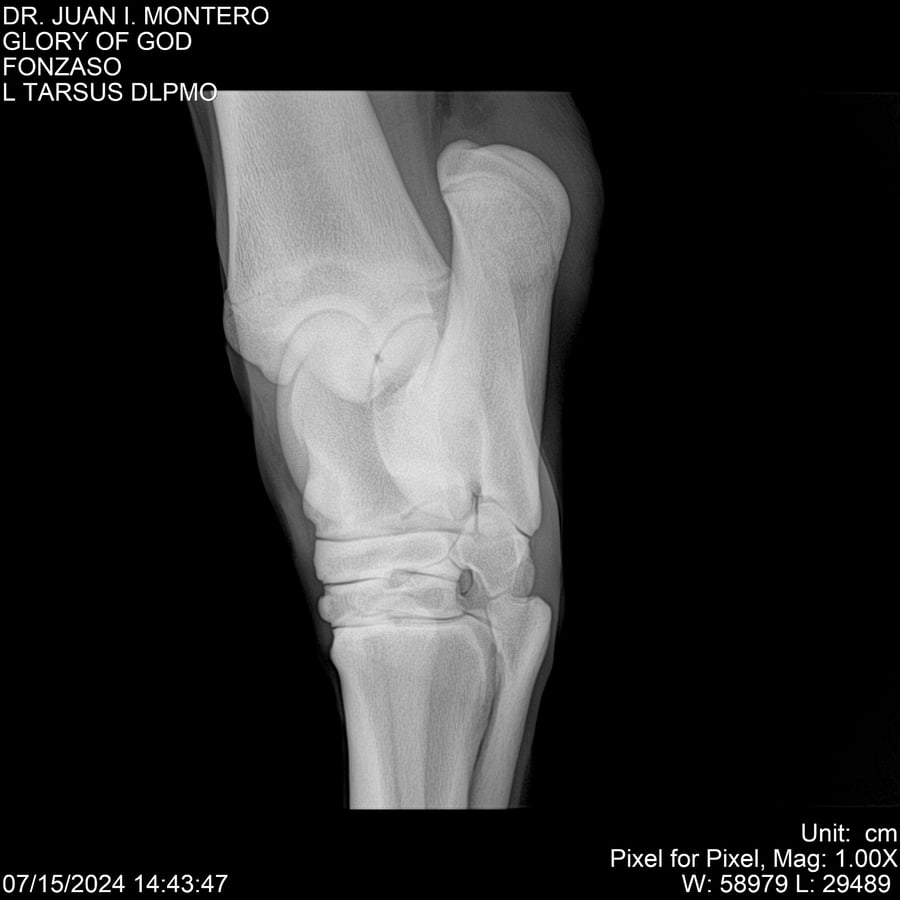

LOTE 10, GLORY OF GOD 🔥 🔥 🔥 Lote Anterior Volver al remate Lote Siguiente Ficha Contacto Montevideo - Ficha del Lote Identificador: #281389 Categoría: Yeguarizos Montevideo - 115 Visualizaciones ClicData Contacto Empresa: Abelenda N. R., Walter Hugo Nombre*: Teléfono* : E-mail* : Mensaje Enviar Registrese gratis Este contenido Exclusivo está disponible sólo para usuarios registrados Ingresar